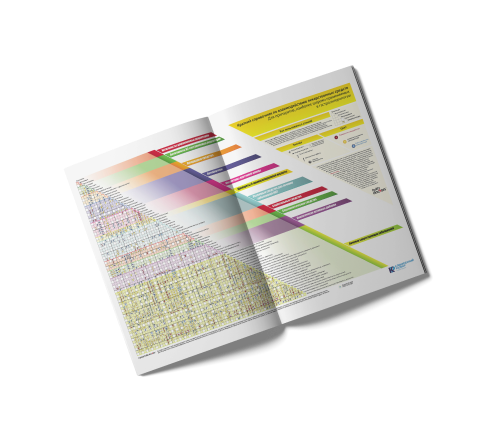

Краткие справочники

по взаимодействию ЛС

по взаимодействию ЛС

Краткие справочники взаимодействия лекарственных средств

+